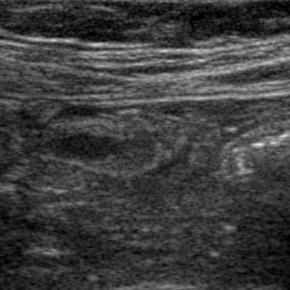

Elastography for the differential diagnosis of malignant versus benign testicular lesions: a meta-analysis

Ziwei Lin, Rui Lin, Huaiyu Wu, Linghu Wu, Jieying Zeng, Jinfeng Xu, Fajin Dong